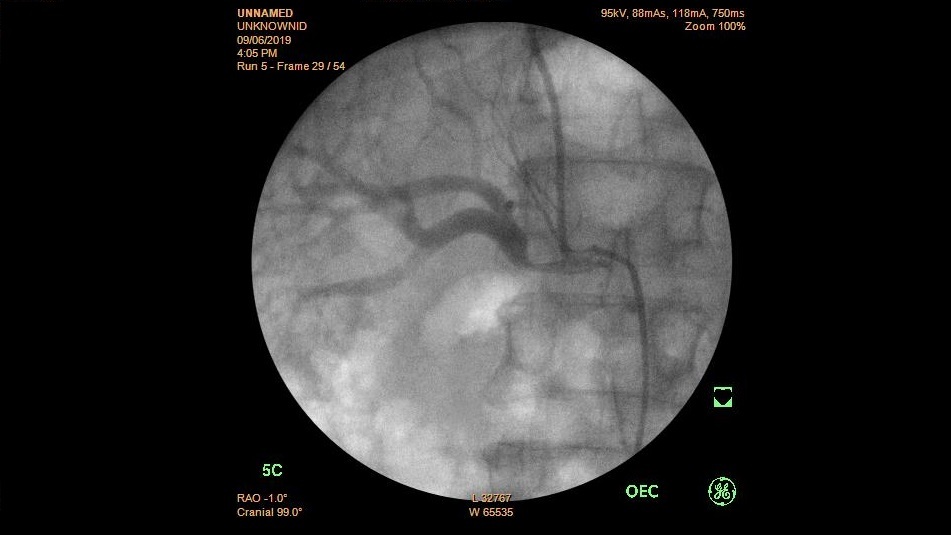

Bệnh viện Trường Đại học Y Dược Huế triển khai thành công phẫu thuật đặt thể hang nhân tạo cho bệnh nhân rối loạn cương nặng

Rối loạn cương là một bệnh lý tuy không nguy hiểm tính mạng nhưng ảnh hưởng rất nhiều đến chất lượng cuộc sống, không chỉ riêng bệnh nhân mà còn với...